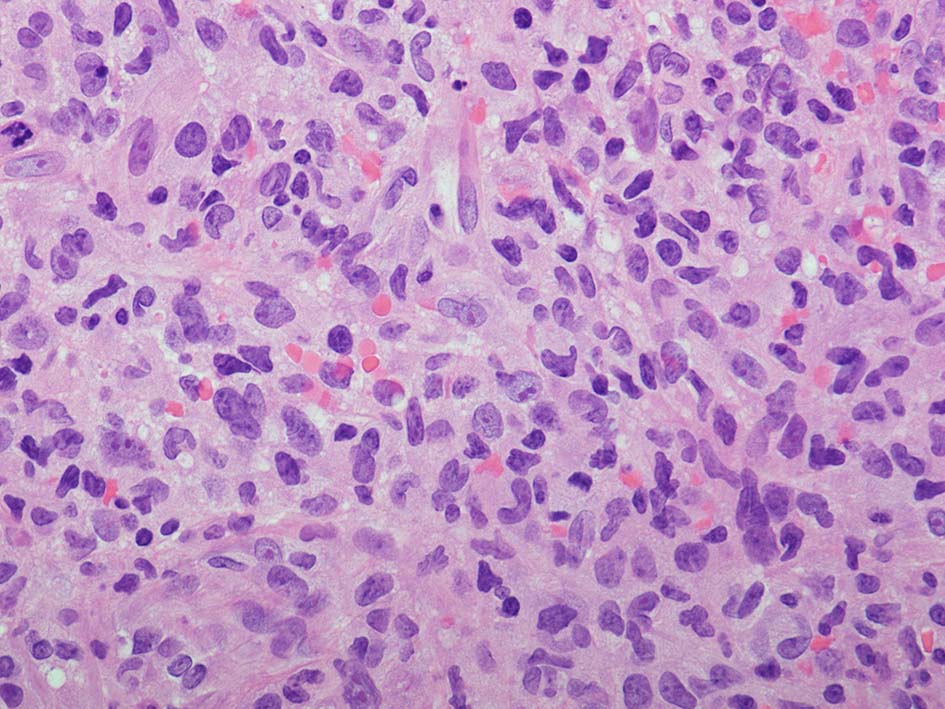

loupe像:表面に痂皮形成. 均等な組織像で,壊死や出血はみられない. 低倍ではspindle cellの密な増殖があるように見える. 拡大所見では, 類円形, 卵円形, ねじれた桿状の核, くびれ,勾玉様の核など不整形な核をもつ細胞が増殖している. クロマチンは繊細な傾向で, 核小体を1個もつ核が認められる. 高倍率10視野で 1-2個の核分裂像が数えられた.

樹状細胞性腫瘍, 組織球性腫瘍, histiocytic sarcoma(あまり異型がめだたない)などを考えて鑑別, 免疫染色をおこなった.

CD20, PAX5, CD3, CD5 リンパ球マーカは陰性. Dendritic cell marker (CD1a, CD123, Langerin, etc)は陰性. S-100, CD168, CD68(KP-1)が陽性. 組織球増殖病変と考えられた. foamy macrophageやgiant cellsはほとんど認められない. 高異型度, 多型細胞の出現はないが, MIB-1 LIが高く, mitosisも増加している, 悪性の心配あり, 治療方針の決定のため consultationを行った.

典型的なJXG細胞は大きく, 細胞質は空胞状で,核は円形または切れ込みをもち, 小さい。細胞は、CD68、fascin、factor XIIIa、CD4で染色されるが、CD1aやCD207(Langerin)では染色されない。*2

Touton giant cellとして知られる、中心部に核を持つ巨細胞が認められる. 時に、emperipolesisが確認される。